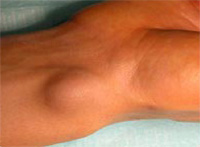

Il s’agit de tuméfactions formées d’une poche remplie d’un liquide gélatineux, développées au voisinage de l’articulation du poignet. La localisation la plus fréquente se situe à la face dorsale du poignet entre les tendons extenseurs du poignet et des doigts, du côté externe. Plus rarement, ils se développent à la face palmaire du poignet dans la gouttière du pouls radial. L’origine provient d’une dégénérescence de la capsule articulaire du poignet plus épaisse et plus résistante dans ces deux localisations.

Le kyste synovial atteint le plus souvent l’adulte jeune (20/30 ans) et de manière à peu près égale chez la femme et l’homme. Il n’épargne pas pour autant l’enfant (de plus de 4 ans) et l’adulte plus âgé (70 ans). Il apparaît habituellement spontanément sans cause particulière et augmente progressivement de volume sur plusieurs mois. Le patient ne s’en aperçoit qu’à la suite d’un traumatisme ou d’un effort violent (ce qui motive la consultation).

![]() |

La tuméfaction peut être de petite taille, à peine visible, mais douloureuse lors des mouvements du poignet ou, au contraire, parfois volumineuse, inesthétique mais totalement indolore. Cette tuméfaction est sphérique, bien limitée, de consistance souvent ferme et plus ou moins mobile par rapport au plan sous-jacent.

La radiographie standard ne montre aucune modification osseuse. L’échographie totalement anodine confirme la nature liquidienne de la tuméfaction et surtout précise les rapports du kyste avec l’artère radiale, pour guider au mieux l’acte chirurgical. Les autres examens tels que IRM, scanner n’ont pas apportés à ce jour la preuve de leur utilité diagnostique ou préopératoire.

Elle est toujours bénigne mais totalement imprévisible. Certains kystes disparaissent spontanément ou à la suite d’une pression. Leur réapparition peut se produire dans un délai très variable (jours, mois, année). Le plus souvent le kyste augmente progressivement de volume pour devenir gênant et douloureux.

Dans la majorité des cas, les kystes synoviaux du poignet ne nécessitent pas de traitement car ils sont peu gênants et souvent de petite taille. S’ils deviennent douloureux (avec une raideur du poignet ou une nette diminution de force), ces kystes justifient un traitement. Différentes méthodes sont possibles tout en sachant que certaines exposent à des taux de récidive relativement importants :